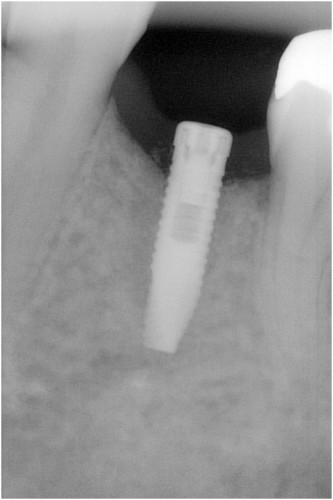

術前

抜歯後

埋入前(抜歯後約6ケ月)

上記、拡大写真

インプラント埋入直前

インプラント埋入時

同拡大

支台装着

被せ物装着

同全体写真